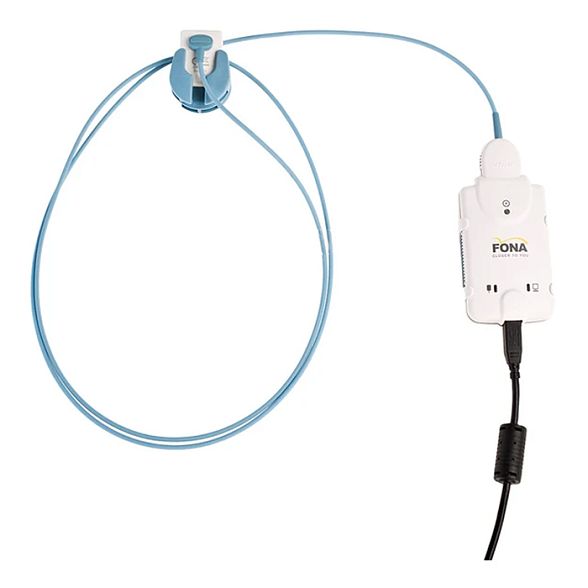

SuniRay2 - система компьютерной радиовизиографии, размер 2

Система компьютерной радиовизиографии SuniRay2 — это современное решение для перехода стоматологической практики на цифровые технологии. Она заменяет традиционную рентгеновскую пленку, обеспечивая мгновенное получение высококачественных изображений при значительно меньшей лучевой нагрузке на пациента.

- Эргономика и комфорт: Датчик размера 2 оптимален для большинства видов внутриротовой рентгенографии. Его тонкая и гладкая конструкция минимизирует дискомфорт для пациента.

| Размер датчика | Размер 2 (примерно соответствует размеру стандартной рентгенопленки №2) |

| Активная область датчика | ~ 30.7 мм x 20.9 мм |

| Подключение к ПК | Через интерфейсную коробку, подключаемую к порту USB |

| Длина кабеля датчика | Достаточная для комфортной работы в кабинете (обычно около 2.5 - 3 метров) |

Вопрос: Что входит в стандартную комплектацию?

Ответ> Обычно в комплект входят: цифровой датчик размера 2, интерфейсная коробка, USB-кабель, программное обеспечение на CD, руководство пользователя, футляр для хранения и транспортировки.